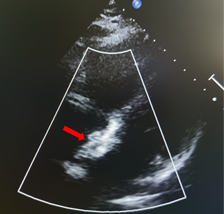

近日,四川省人民医院心脏超声与计算心脏病学团队、结构性心脏病团队于《Quantitative Imaging in Medicine and Surgery》分享的病例,通过多模态超声精准识别舒张期二尖瓣与三尖瓣反流,并成功通过希氏束起搏实现血流动力学逆转,为临床提供了宝贵的诊断与治疗思路。